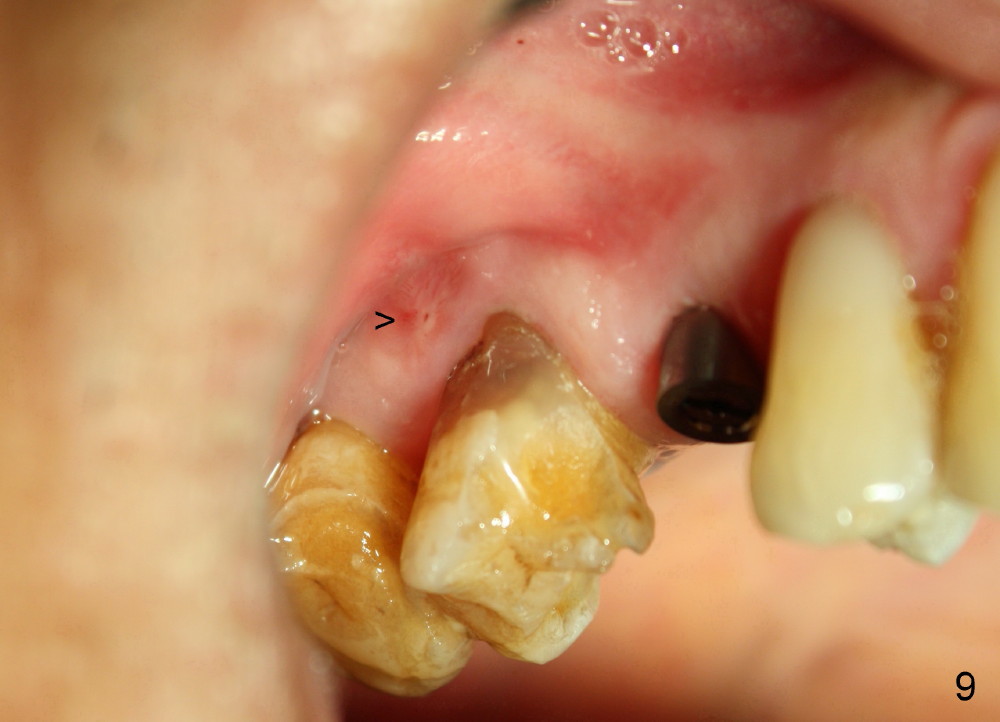

A 72-year-old man is a bruxer with #3 cusp fracture with chronic periapical radiolucency (Fig.1 *) and #4 acute crack. It appears reasonable to take care of emergency (#4 extraction and immediate implant (Fig.3-7: 4.5x20 mm, 45 Ncm)) followed by root canal therapy or extraction for #3. Eight (Fig.8) and 14 (Fig.9-11) days postop, the patient is doing fine and the wound heals normally. But he does not agree any treatment for #3, since it is asymptomatic in spite of a fistula associated with the tooth (Fig.8,9 >). Three months postop, the patient is still asymptomatic and is ready for #4 restoration since the tooth #28 cracks. Follow-up PA shows the persistent distal gap (Fig.12 >, as compared to Fig.4), accompanied with crestal bone resorption (*). Clinically the implant has mild mobility and light tenderness. The patient still refuses #3 treatment. It appears that the implant has failed to osteointegrate. In brief, do not place an immediate implant next to active infection.